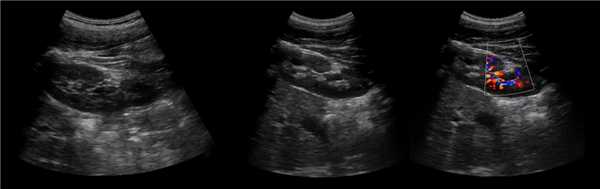

Рисунок. У новорожденного на УЗИ почек определяется гидронефроз (1) и расширенный мочеточник (2) справа. В мочевом пузыре двустороннее уретероцеле (3). При исследовании левой почки структурных изменений не выявлено.

Рисунок. На УЗИ определяется удвоенная чашечно-лоханочная система, расширена лоханка верхнего сегмента (1) и мочеточник на всем протяжение (2, 3), в мочевом пузыре уретроцеле (4). Полное или неполное удвоение чашечно-лоханочной системы возможно увидеть с помощью КТ-урографии.